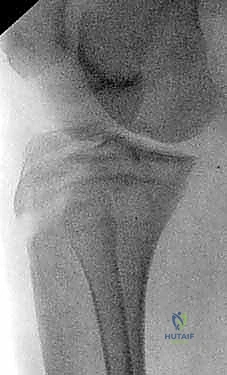

2. التصوير بالأشعة السينية (X-Rays)

هو الخطوة التشخيصية الأساسية. يتم أخذ صور من زوايا متعددة (أمامية خلفية AP، وجانبية Lateral). الصورة الجانبية هي الأكثر أهمية لأنها تظهر بوضوح مدى انفصال (انزياح) حدبة الظنبوب عن مكانها الطبيعي، وتظهر أيضاً ارتفاع الرضفة (Patella Alta).